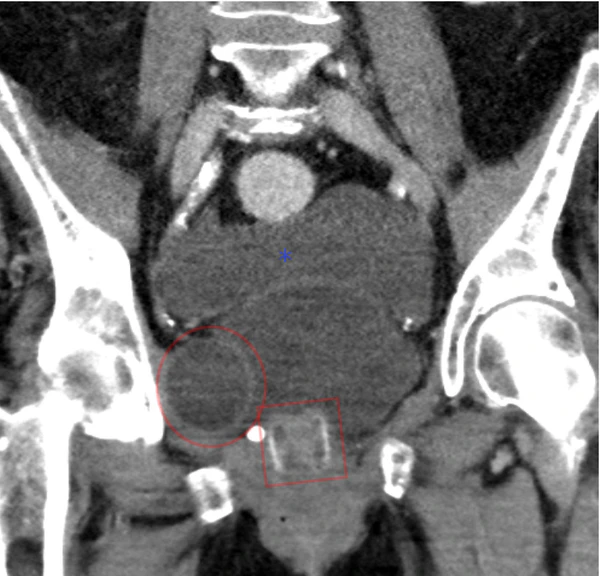

- Искусственный сфинктер с баллонным резервуаром или 3-компонентным устройством: манжета, помпа и баллон. Манжета располагается вокруг мочеиспускательного канала, помпа помещается в мошонку, а баллонный резервуар имплантируется в ретропубическое пространство — между мочевым пузырем и подвздошной веной. Давление в гидравлической цепи создается эластичным баллонным резервуаром и давлением из ретропубического пространства.[1]

Фредерик Фолей был первым, кто описал искусственный сфинктер мочевого пузыря для лечения недержания мочи с наружным расположением, опубликовано в 1947 году.[5] В 1972 году Ф. Брантли Скотт и его коллеги из Медицинского колледжа Бейлора разработали первый предшественник современного искусственного мочевого сфинктера.[6][7] Первой моделью ИСМП, появившейся на рынке, является AMS 800 (Boston Scientific, Массачусетс, США), которая была разработана 50 лет назад.[8][9] Это трехкомпонентное устройство с манжетой, располагающейся вокруг мочеиспускательного канала, помпой, вставляемой в мошонку, имплантируемым в таз резервуаром для создания давления, который поставляется в виде набора для подготовки и наполнения перед имплантацией.[10]

Другой моделью ИСМП является ZSI 375 (Zephyr Surgical Implants, Женева, Швейцария), представлена в 2008 году.[11] Это цельное двухкомпонентное устройство с манжетой и помпой со встроенной пружиной. Оно поставляется как единое целое, предварительно соединенным и заполненным.[1][12] В ZSI 375 нет брюшного компонента, что наряду с его полной готовностью к имплантации сокращает операционное время.[13] Кроме того, отсутствие абдоминального разреза позволяет избежать постоперационного рубцевания а забрюшинном пространстве.[14][15] Еще одним преимуществом модели ZSI 375 является возможность увеличивать или уменьшать давление внутри устройства после имплантации для достижения желаемой степени сдерживания и удовлетворенности пациента. В частности, эти корректировки помогают контролировать сдерживание мочи в случае постимплантационной уретральной атрофии или задержки мочи (плохой отток мочи).[16][17][13] Регулировка давления может быть выполнена в амбулаторных условиях путем добавления или удаления дополнительного стерильного физиологического раствора при помощи шприца через мошонку.[12] К 2019 году во всем мире было имплантировано более 4,500 искусственных сфинктеров мочевого пузыря ZSI 375.[11]